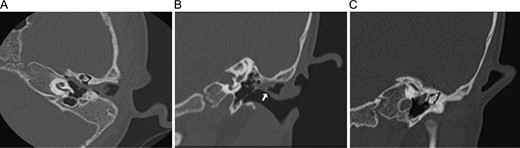

Computed tomography (Fig. 2) revealed the ear canal polyp with a stalk extending to the middle ear. A fistula was seen in the external auditory canal. Also seen were ipsilateral malformed malleus and incus, a small epitympanum, and either thickening of the tensor tympani tendon into the mass or lack of tensor tendon.

CT of the temporal bones without contrast, with bone windowing. (A) Axial scan showing the mass extending into the middle ear, past the ossicles and toward the eustachian tube. (B) Coronal scan revealing the fistula of the external auditory canal (arrow), with the mass extending from that area into the middle ear. (C) Coronal scan with small epitympanum and ossicular view.